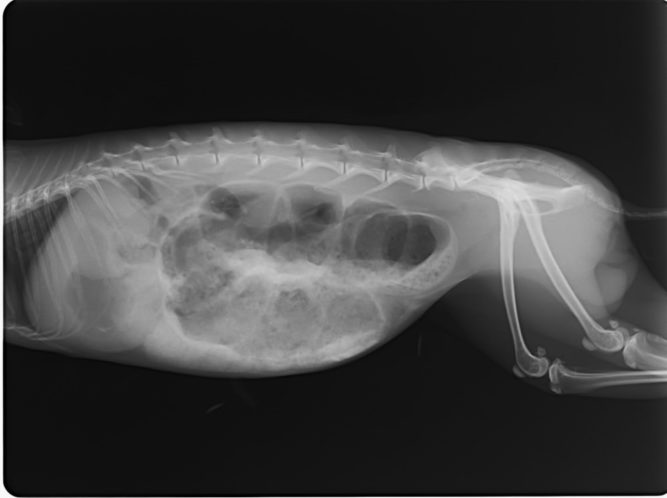

Fiatal félig sziámi cica kezelése. A panaszai régóta a szemhéj szél, orrtükör sarka és szájszél pörkösödése, váladék felrakódása. Elsőként kap Imunovet, Virovet cseppet, és Cytovet 200 ml-ben higítottat itatnak napi 5 ml-t. A két hét alatt javult, a szeme és szája is szebb…